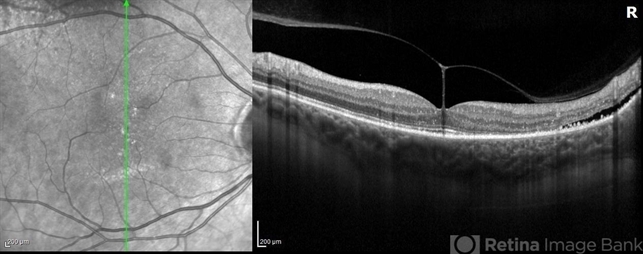

- vitreomacular traction (VMT), optical coherence tomography (OCT), vitreomacular adhesion, vitreomacular interface disorders, OD, right eye, heidelberg spectralis, subretinal fluid

Optical coherence tomography system

Heidelberg Spectralis

- Optical Coherence Tomography (OCT) of a 69 year old male with Vitreomacular Traction affecting his right eye. Patient was referred to this office for Choroidal Melanoma in his right eye in May 2021. The patient was treated with Brachytherapy in July 2021 and this OCT was taken at a follow-up appointment in May 2022. Patient's vision was 20/30-2 at the time this OCT was taken. Patient states that his vision was better since his last visit, and that he sees floaters occasionally.